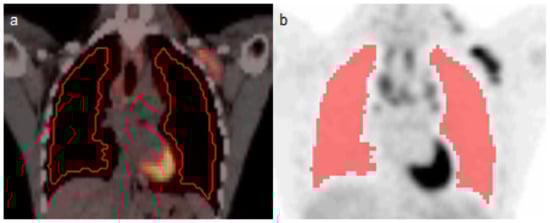

2.2. 18F-FDG PET/CT Analysis

2.3. PET Radiomics